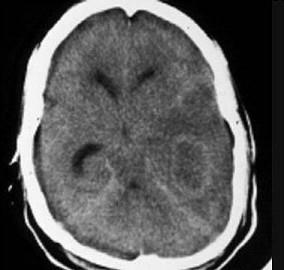

问题 一男患者,39岁,头痛、呕吐、发热3天,脑膜刺激征(+)头颅CT表现如图,最可能的诊断是 ( )

选项 A、弓形体感染 B、化脓性性脑膜炎 C、真菌性脑膜炎 D、螺旋体感染 E、结核性脑膜炎 一、单项选择题

答案 E